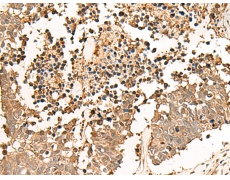

IHC positive control:

Human esophagus cancer and Human lung cancer

IHC Recommend dilution:

30-150